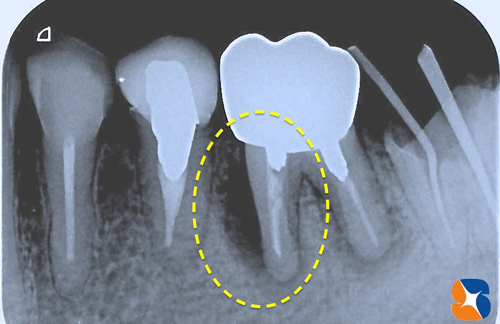

40代の女性、御紹介で来院。主訴は、「奥から2番目(=黄色の点線)の歯が浮いた感じがする。歯肉も定期的に腫れるので、職場近くの医院で診てもらったら“抜歯して入れ歯かブリッジになる”と言われた。インプラントは、トラブルも多いと聞くのであまり考えていない。」でした。

〈CT撮影の結果〉

DR.「このまま放置すれば、ますます黒い影の部分(膿の袋)が大きくなって、他の歯の周囲骨にも波及します。抜歯後、入れ歯にすれば、今までのように強く噛めません。ブリッジにした場合は、支える2本の歯に負担がかかり過ぎるため遠い将来、何らかのトラブルが生じやすくなります。

CT撮影での予測通り、ほっぺた側の骨を中心に大きく欠落していました。